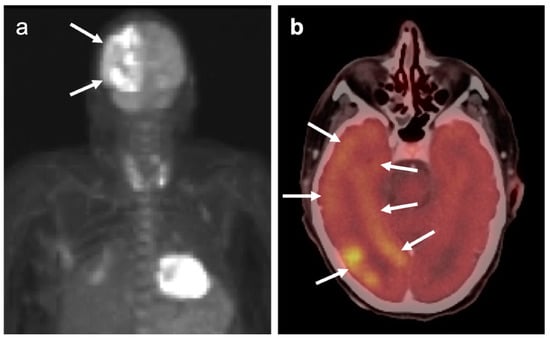

2.3. Nasopharyngeal Carcinoma

3.2. Paraneoplastic CNS Manifestations and Sources of False Positive FDG PET Scans That Can Mimic Brain Tumors

3.3. Primary Brain Tumors

3.4. CNS Lymphoma

3.5. Brain Metastases